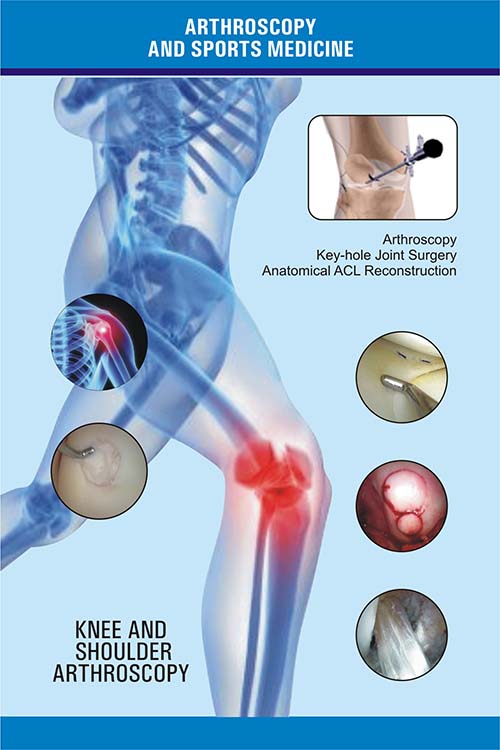

Arthroscopy is a common surgical procedure in which a joint (arthro) is viewed (scopy) using a small camera. Arthroscopy gives doctors a clear view of the inside of the knee. This helps them diagnose and treat knee problems. Technical advances have led to high definition monitors and high resolution cameras. These are other improvements have made arthroscopy a very effective tool for treating knee problems.

At Shree Datta Hospital arthroscopy is commonly performed for treating meniscus injury, reconstruction of the anterior cruciate ligament and for cartilage microfracturing. Arthroscopy can also be performed just for diagnosing and checking of the knee. However, the latter use has been mainly replaced by magnetic resonance imaging.

During an average knee arthroscopy, a small fiberoptic camera (the arthroscope) is inserted into the joint through a small incision, about 4mm(1/8 inch) long. A special fluid is used to visualize the joint parts. More incisions might be performed in order to check other parts of the knee. The other miniature instruments are used and the surgery is performed.

All sort of treatment and modalities available for sport injuries with the help of physiotherapy early rehabilitation of the injured person possible for easy and fast recovary all sort of ligament repair done here arthroscopic and minimal invasive surgeries available intraarticular injections imported plasters all available